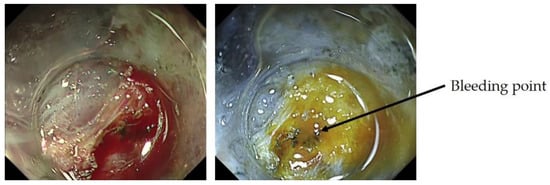

- Yorita, N.; Oka, S.; Tanaka, S.; Kotachi, T.; Nagasaki, N.; Hata, K.; Kuroki, K.; Masuda, K.; Kurihara, M.; Kiso, M.; et al. Clinical Usefulness of Dual Red Imaging in Gastric Endoscopic Submucosal Dissection: A Pilot Study. Clin. Endosc. 2020, 1, 54–59. [Google Scholar] [CrossRef] [PubMed] [Green Version]